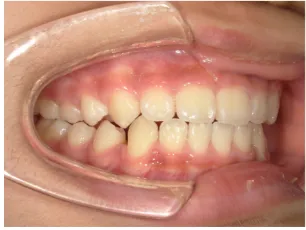

治療中③小2(7y8m):JUMP 受け口が改善

治療中④小2(8y2m)~小3(9y1m):QHとBHで拡大・アーチ形態の修正、ブラケットで前歯の並べ替えまで終了

| 行ったご提案・診断内容 | 成長期に行う治療と咬合治療をご提案 受け口用ファンクショナルアプライアンス(写真②③)からスタートし、小2以降で上下顎の拡大・歯列弓の形態修正・前歯の並べ直し(写真④)を行いその後、モノブロック(筋機能的咬合誘導)装置(写真⑤)へ移行し、受け口の再発予防と永久歯を適切な咬み合わせに誘導し、必要によりマルチブラケット法へ移行する治療方法を提案しました。 成長期治療(成長時期にお口の環境を整える治療) 2年生以降から 咬合治療 |

| 治療期間 | 12か月:受け口用ファンクショナルアプライアンス(写真②③) 12カ月:成長期治療の動的治療期間(写真④) 現在、成長の経過観察と咬合誘導中です(写真⑤~⑨) |